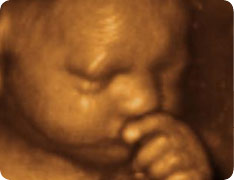

С появлением 3д и 4д УЗИ мы можем заглянуть «за грань» и довольно отчетливо следить за происходящим. И оказывается, что довольно часто на сеансах УЗИ пузожители прикрываются ручками, сжимаются в комочек, пытаются спрятаться, «убежать»! То есть, ведут себя так, словно им происходящее страшно не нравится.

4d УЗИ при беременности, еще один малыш закрывающий лицо ручками